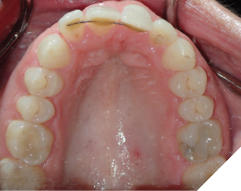

The majority of the orthodontic practices offer a period of “supervised retention” to their patients and communicates the customized retention recommendation with the patient’s general dentists. It is extremely important to work as a team to achieve long term clinical success in maintaining a functional bite and aesthetic smile. The general dentists continue to see their patients on a regular basis and have an opportunity to assess the orthodontic retainers and the bite after the supervised retention period is completed by the orthodontists. With great care, orthodontic retainers would serve for a long time (Fig. 1) without any major issues. However, in some cases, the failure to notice the clinical problems early on results in functional issues that would require a comprehensive orthodontic treatment to correct it (Fig. 2).

Fig. 1A

Fig. 1B

Fig. 1C